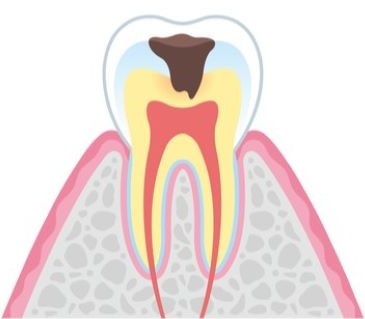

むし歯の進行度と治療法

CO

COはエナメル質の初期段階での損傷を指し、目に見える穴はなく、白く濁ったりツヤがなくなったりする状態です。痛みはなく、適切なブラッシングとフッ素の活用で再石灰化が可能になることが多いため、削る治療は行わず経過観察が一般的です。定期検診を受けることで進行を抑え、自然治癒を促します。

COはエナメル質の初期段階での損傷を指し、目に見える穴はなく、白く濁ったりツヤがなくなったりする状態です。痛みはなく、適切なブラッシングとフッ素の活用で再石灰化が可能になることが多いため、削る治療は行わず経過観察が一般的です。定期検診を受けることで進行を抑え、自然治癒を促します。

C1

C1では、むし歯がエナメル質まで進行し小さな穴が開くことがあります。痛みを感じることは少ないものの、冷たいものがしみることがあるため注意が必要です。この段階では、むし歯の部分を最小限に削り、白いレジンで修復します。1回の治療で終了することがほとんどです。

C1では、むし歯がエナメル質まで進行し小さな穴が開くことがあります。痛みを感じることは少ないものの、冷たいものがしみることがあるため注意が必要です。この段階では、むし歯の部分を最小限に削り、白いレジンで修復します。1回の治療で終了することがほとんどです。

C2

C2になると、むし歯がエナメル質を超えて象牙質まで達し、痛みや食事時の不快感が現れます。穴に食べ物が詰まりやすく、さらに進行するリスクが高まるため、早急な治療が求められます。治療では、象牙質を削り、ハイブリッドレジンやメタルインレーを用いて詰め物を行います。

C2になると、むし歯がエナメル質を超えて象牙質まで達し、痛みや食事時の不快感が現れます。穴に食べ物が詰まりやすく、さらに進行するリスクが高まるため、早急な治療が求められます。治療では、象牙質を削り、ハイブリッドレジンやメタルインレーを用いて詰め物を行います。

C3

C3段階では、むし歯が神経(歯髄)にまで達しているため、ズキズキする痛みが続きます。冷たいものや熱いものに敏感になり、夜間も眠れないほどの痛みを引き起こすことがあります。この段階の治療では、根管治療が必要です。当院では、ラバーダムを使用して治療中の唾液や細菌の侵入を防ぎ、徹底した消毒を行います。(※ラバーダムの使用は、症例によって異なります。)

C3段階では、むし歯が神経(歯髄)にまで達しているため、ズキズキする痛みが続きます。冷たいものや熱いものに敏感になり、夜間も眠れないほどの痛みを引き起こすことがあります。この段階の治療では、根管治療が必要です。当院では、ラバーダムを使用して治療中の唾液や細菌の侵入を防ぎ、徹底した消毒を行います。(※ラバーダムの使用は、症例によって異なります。)

C4では、歯の大部分が失われ、神経が死んでいるため痛みは一時的に感じませんが、膿が溜まりやすく、顎の腫れや強い痛みを引き起こします。場合によっては周囲の骨が溶け出し、隣接する歯にも影響が及ぶことがあります。抜歯が必要な場合も多く、その後はインプラント、ブリッジ、入れ歯などで咀嚼機能を回復させます。

C4では、歯の大部分が失われ、神経が死んでいるため痛みは一時的に感じませんが、膿が溜まりやすく、顎の腫れや強い痛みを引き起こします。場合によっては周囲の骨が溶け出し、隣接する歯にも影響が及ぶことがあります。抜歯が必要な場合も多く、その後はインプラント、ブリッジ、入れ歯などで咀嚼機能を回復させます。